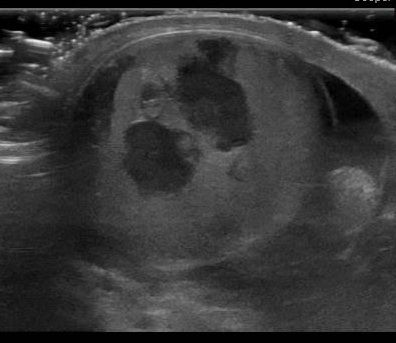

What’s the Diagnosis? Gepost op 3 januari 20183 januari 2018 door netwerkvsseh What’s the Diagnosis? @emdaily.cooperhealth.org Dit delen: Delen op X (Opent in een nieuw venster) X Share op Facebook (Opent in een nieuw venster) Facebook Delen op LinkedIn (Opent in een nieuw venster) LinkedIn E-mail een link naar een vriend (Opent in een nieuw venster) E-mail Afdrukken (Opent in een nieuw venster) Print Vind-ik-leuk Aan het laden... Gerelateerd